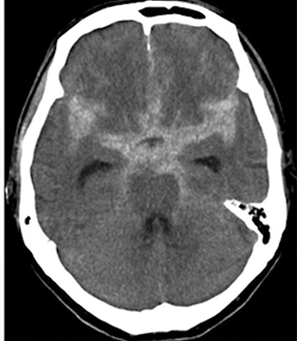

55歳女性。2~3日前から続く頭痛で来院。頭部CT施行。

診断:右Sylvius裂の溝が不明瞭。やや高吸収域を認めクモ膜下出血。

2~3日経っていたから典型的な所見とは解離して映っている。このパターンも覚えておく。